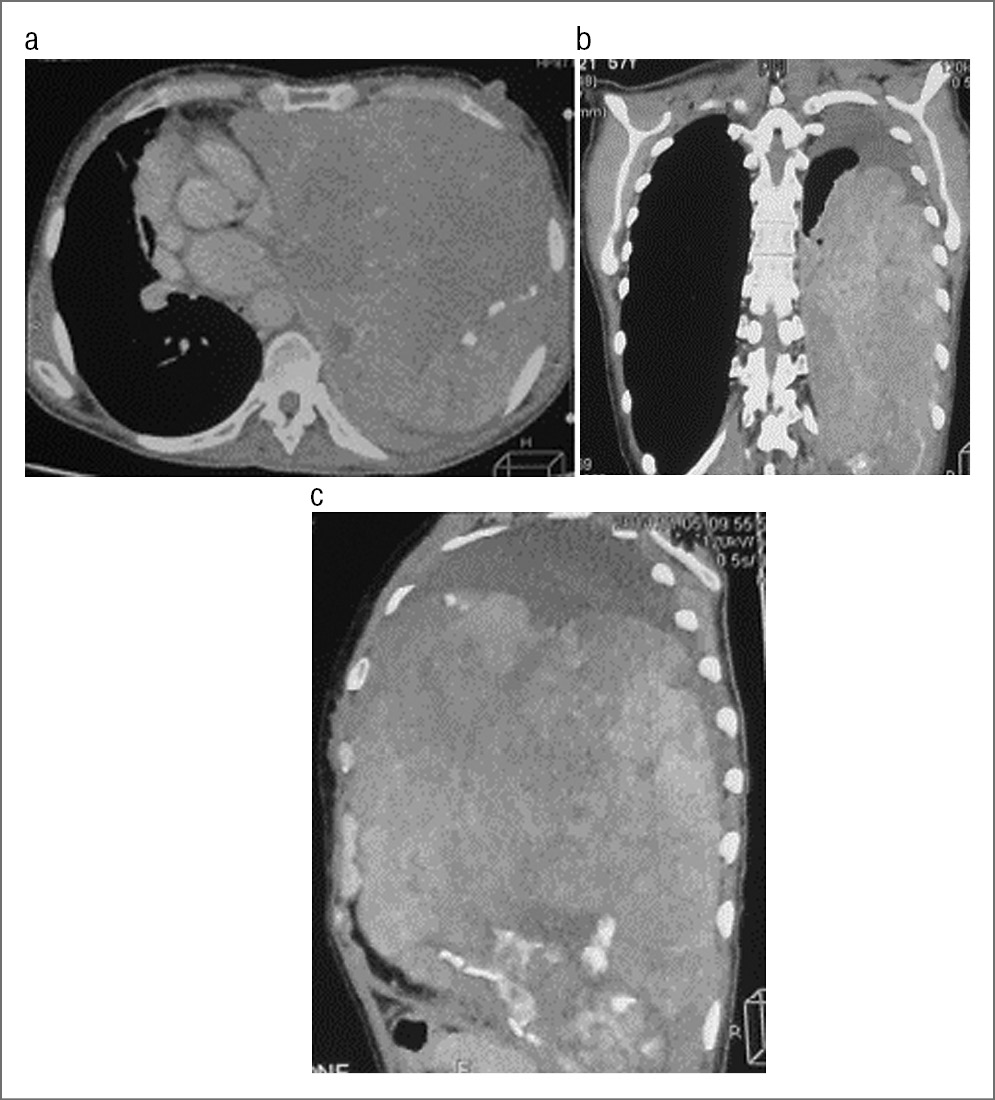

Пациент Ш., 45 лет. Диагноз: саркома левого гемиторакса 4T2bNxM1. Солитарный метастаз саркомы в правую долю печени. Жалобы на одышку при средней физической нагрузке. Анамнез: постепенно нарастающая одышка, кашель с отхождением умеренного количества мокроты. При МСКТ выявлены левосторонний гидроторакс, опухоль левого гемиторакса, единичный очаг правого легкого (рис. 6). Поступила в отделение торакальной хирургии УКБ №1 для дообследования и определения дальнейшей тактики лечения.

Рис. 6. a, b – МСКТ в аксиальной проекции; c – МПР.

После дообследования проведена операция: торакотомия слева, удаление опухоли левого гемиторакса. Отмечалось гладкое течение послеоперационного периода, пациентка выписана в удовлетворительном состоянии.